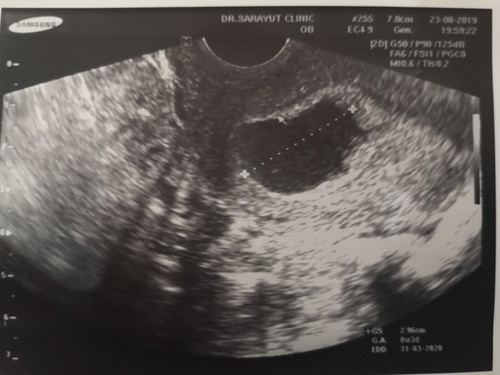

วันนี้ไปซาวด์มา อายุครรภ์ 6 สัปดาห์ เจอแต่ถุงตั้งครรภ์ไม่เจอเด็กหมอบอกน่าจะท้องลมค่ะ เพราะถุงตั้งครรภ์โตกว่าปกติซึ่ง 6 สัปดาห์ไม่ควรเกิน 2 เซนต์ แต่วันนี้วัดได้ 2.9 เซนต์ แม่ๆคนไหนเคยเป็นแบบนี้บ้างคะ ท้อมากเลยค่ะปล่อยมา 3 ปี แล้วกว่าจะท้อง พอมีหวังจะเจอตัวน้องบ้างไหมคะ